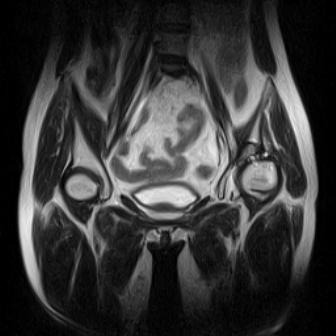

片子不全,应该是左侧股骨头无菌坏死,右侧似乎没问题,到正规医院治疗,千万别看广告去小医院,吃中药什么的,都是骗人的(说了也白说,百分百都得让人骗点钱才甘心。)

应该是左侧股骨头无菌坏死